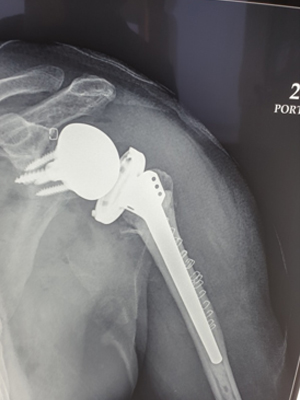

Post Surgery X-ray for Rotator Cuff Arthopathy

Post Reverse Shoulder

Replacement Suregry X-ray